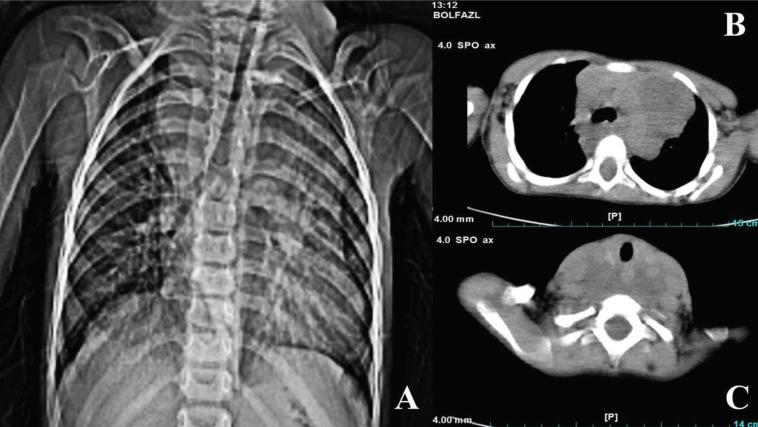

Neurofibromatosis type 1 (NF1) is an autosomal dominant disease diagnosed with the presentation of café-au-lait macules, skinfold freckling, iris Lisch nodules, neurofibromas, osseous lesion, and optic gliomas. Mediastinal mass as the first presentation of NF1 is very rare, with a frequency of about 2.7%. Here, we present a rare case of NF1 in a 3-year-old boy admitted with respiratory distress and superior vena cava syndrome.

1型神经纤维瘤病(NF1)是一种常染色体显性疾病,通过咖啡斑、皮肤褶皱雀斑、虹膜Lisch结节、神经纤维瘤、骨病变和视神经胶质瘤等表现来诊断。纵隔肿块作为NF1的首发表现非常罕见,发生率约为2.7%。在此,我们报告一例罕见的NF1病例,患者为一名3岁男孩,因呼吸窘迫和上腔静脉综合征入院。